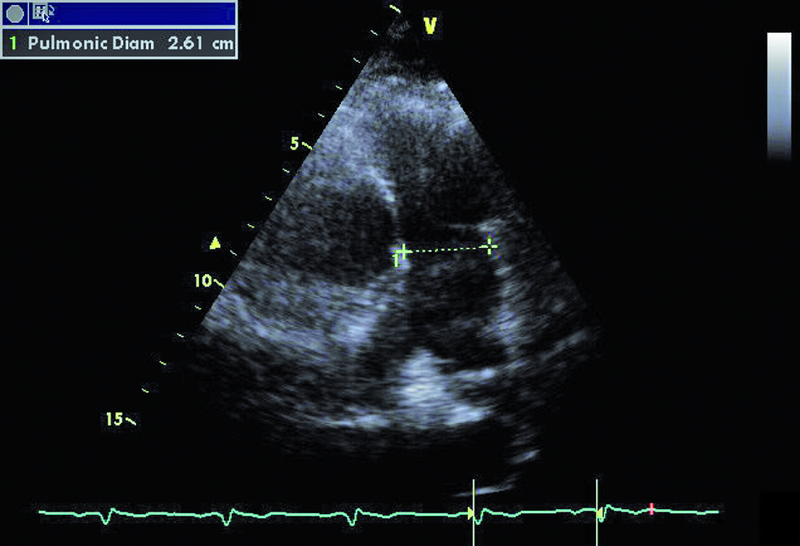

W badaniu echokardiograficznym zwrócono uwagę na powiększenie jamy lewej komory z nieznacznie upośledzoną kurczliwością mięśnia (ryc. 1). Stwierdzono także trójpłatkową zastawkę aortalną (ryc. 2) ze śladową niedomykalnością oraz małą niedomykalność mitralną. Te nieprawidłowości nie mogły tłumaczyć szmeru ciągłego w badaniu fizykalnym ani też nieznacznie powiększonej sylwetki serca. Przyczyną szmeru ciągłego jest najczęściej przetrwały przewód tętniczy Botalla, łączący aortę i pień płucny. Połączenia takiego jednak w miejscu typowym nie znaleziono. Rejestrowano u chorego prawidłową średnicę pnia płucnego (ryc. 3) oraz nieznacznie przyspieszoną prędkość wypływu płucnego (ryc. 4). Szmer ciągły nakazywał poszukiwać innych rzadkich połączeń między dużymi naczyniami. Jedną z nich jest okienko aortalno-płucne, czyli tzw. fenestracja aortalno-płucna, i tę wadę właśnie rozpoznano u chorego.